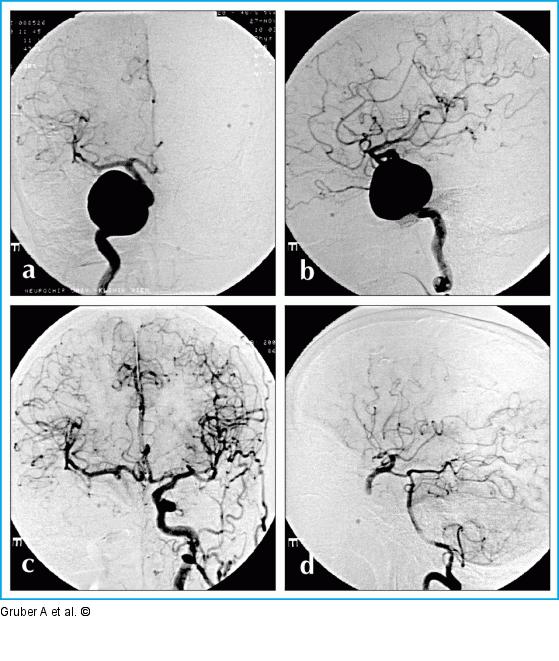

Abbildung 10a-d: Therapeutischer endovaskulärer Gefäßverschluß Therapeutischer endovaskulärer Gefäßverschluß (PAO, "Parent artery occlusion") bei intrakavernösem Riesenaneurysma der A. carotis interna rechts (a, b). Nach Ballontestokklusion (BTO) über 30 Minuten ist der proximale Gefäßverschluß mit absetzbaren Ballons bei angiographisch dokumentierter guter Kollateralkreislaufsituation (A. communicans anterior-cross flow [c], A. communicans posterior-cross flow [d]) ohne vorbereitende Revaskularisationsoperation möglich. |